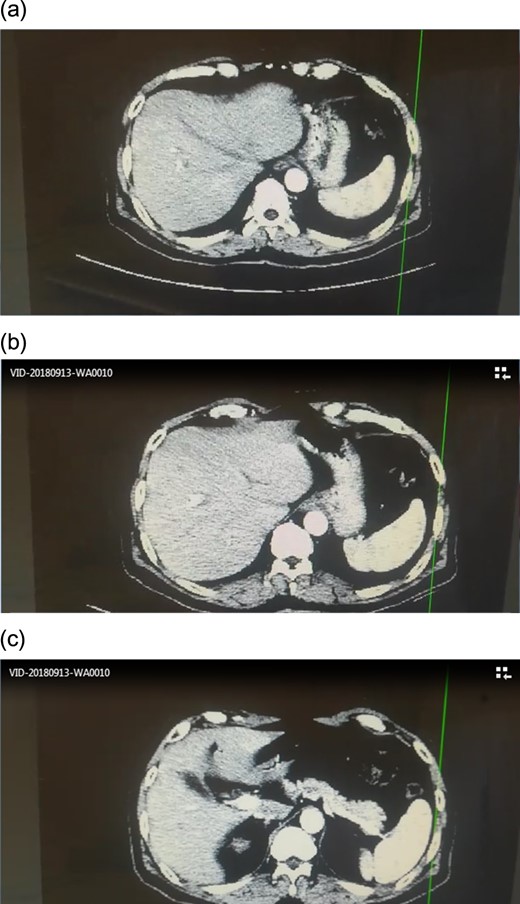

CT scan showed no signs of metastasis (Fig. 1).

Angiographic CT after procedure confirmed the absence of celiac trunk, the absence of left gastric, the splenic artery arising from aorta directly and common hepatic artery arising from superior mesenteric artery.(Fig. 3)